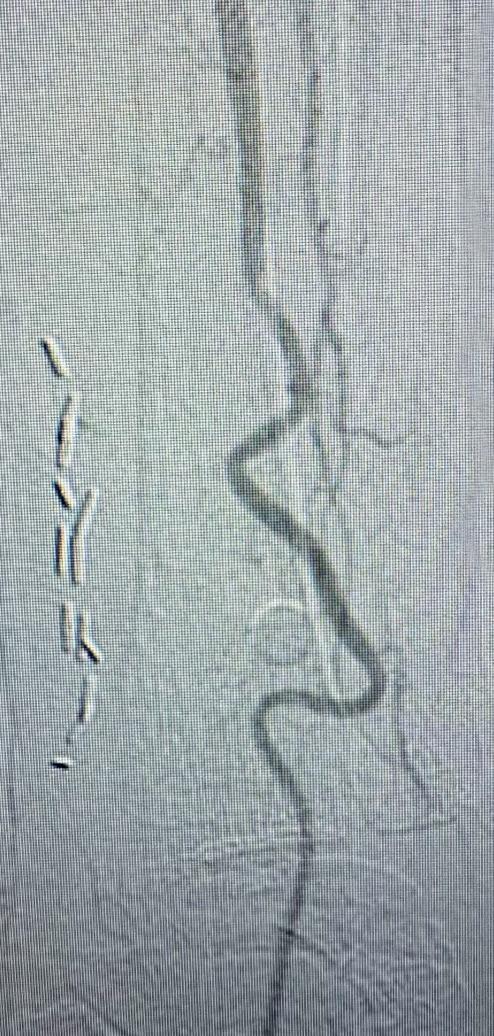

Arteriogram, left lower extremity

An arteriogram of the left lower extremity was performed via antegrade left common femoral artery access based on preoperative review of the lower extremity arteriogram from Uzbekistan. Scattered non-calcified plaque with moderate to high-grade stenoses were identified in the proximal and mid superficial femoral artery. Diffuse severe calcified tibial artery disease was identified. There was a long segment stenosis of the proximal and mid posterior tibial artery coupled with a more distal occlusion. The proximal peroneal artery was calcified and occluded with distal reconstitution identified. There was complete occlusion of the anterior tibial artery (Figure 2).

Shockwave E8 3mm x 80mm to the posterior tibial artery

The posterior tibial artery was successfully crossed first. The long-length posterior tibial artery disease was treated with a Shockwave E8 3.0mm x 80mm IVL catheter, with no pre-dilatation required. A total of 200 pulses were delivered along the length of the posterior tibial artery (Figure 3).

Shockwave E8 3mm x 80mm to the peroneal artery

Following this, the peroneal artery occlusion was successfully crossed. The longlength peroneal artery disease was treated with the same Shockwave E8 3mm x 80mm IVL catheter also with no pre-dilatation required. The remaining 200 pulses were

delivered across the length of the peroneal artery disease (Figure 3).

Left SFA intervention

To ensure adequate inline blood flow to the tibial vessels, the SFA disease was treated with drug-coated balloon angioplasty, followed by self-expanding stent placement.

Post-intervention arteriogram

An excellent technical result was achieved. The SFA was widely patent with no significant residual stenosis. The posterior tibial and peroneal arteries were widely patent with brisk flow and no residual stenosis. Significantly improved flow was identified to the foot (Figure 4).